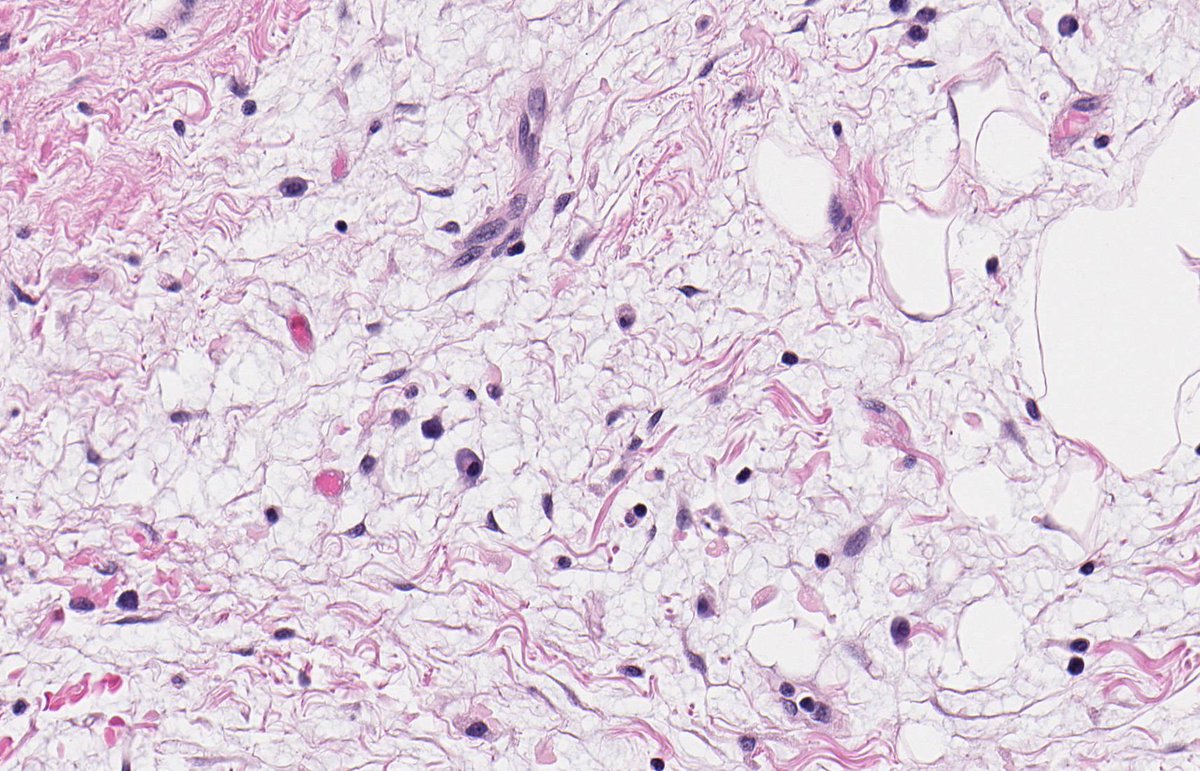

PERINEPHRIC MYXOID PSEUDOTUMOUR OF FAT. NB: sheets of mature adipocytes; spindle-stellate cells in myxoid stroma; mild chronic inflammatory infiltrate; MDM2 non-amp; may arise in context of renal cell disease and transplantation (PMID: 19525929, 30826321, 33835530).